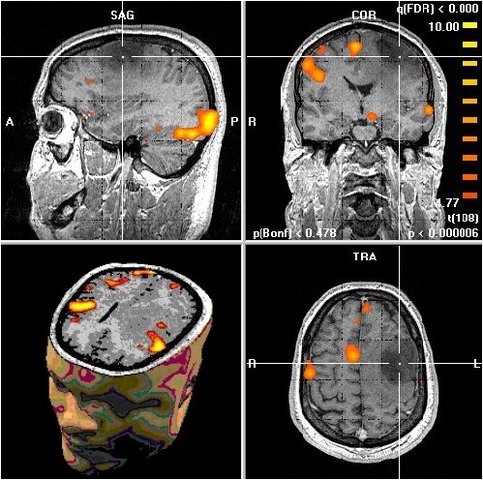

• Aplicación de la Resonancia Magnética

Aplicación de la Resonancia Magnética

La aplicación de la resonancia magnética para el estudio médico y diagnóstico con imágenes obtenidas del cerebro permitió detectar los cambios en la distribución del flujo sanguíneo cuando el individuo desarrolla tareas sensoriales o motoras, o en distintos paradigmas cognitivos, emocionales y de motivación.